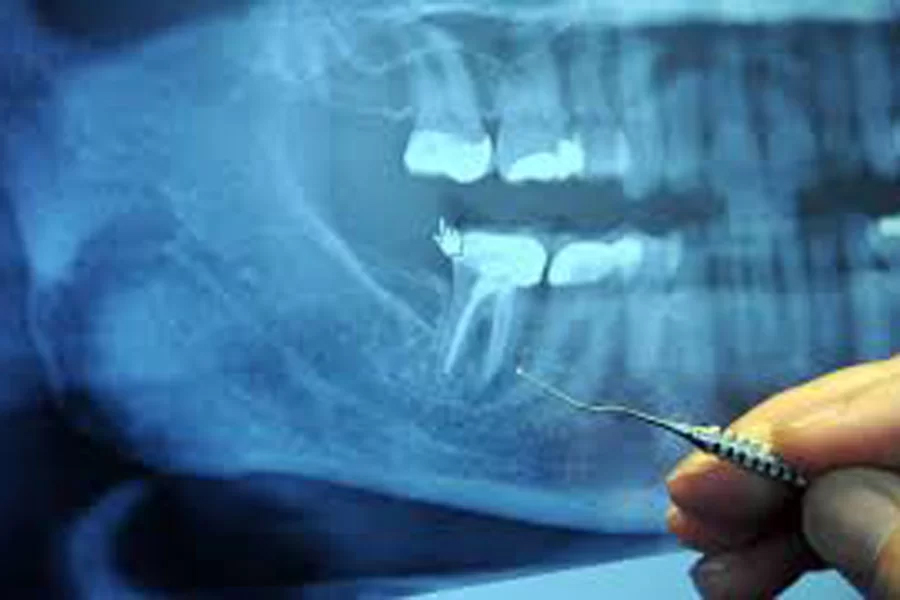

レントゲン

歯科医院で撮影されるレントゲンはお口の部分のみにあたりますので、おなかの中の赤ちゃんへの影響はほとんどございません。

とはいえ、やはり、本当に大丈夫なのかと気にされる方はとても多くいらっしゃいます。

そのような不安や心配、ストレスなどはおなかの中の赤ちゃんにとっても良い影響を及ぼしませんので、当院では妊婦さんの治療の場合、レントゲン撮影はなるべく控えるようにしております。

どうして撮影が必要な場合においても、まずはご説明・相談させていただきますのでどうぞご安心ください。